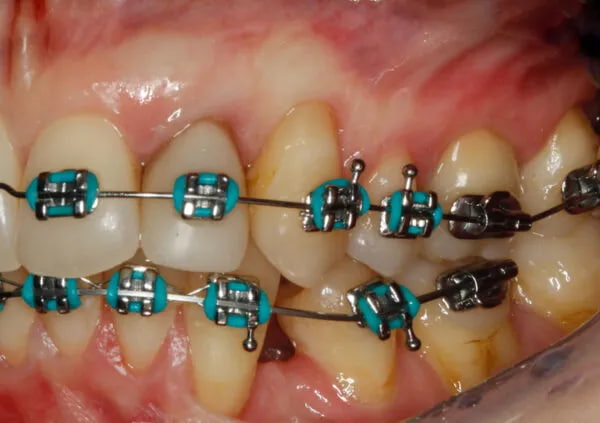

Leczenie kompleksowe, kortykotomia

Kompleksowe leczenie pacjenta z zapaleniem przyzębia może obejmować leczenie implantologiczne, protetyczne oraz ortodontyczne. Moduł VIII jest dedykowany zabiegom chirurgicznym na pograniczu różnych dyscyplin.

- Augmentacja tkanek miękkich przed leczeniem ortodontycznym i po leczeniu ortodontycznym.

- Kortykotomia.

- Leczenie ortodontyczne w terapii kompleksowej: planowanie ruchu zęba, leczenie pacjentów z zapaleniem przyzębia.

- Planowanie uśmiechu we współpracy z lekarzem protetykiem z wykorzystaniem narzędzi cyfrowych.

- Chirurgiczne wydłużanie koron klinicznych zębów ze wskazań protetycznych: przekroczenie szerokości biologicznej, gingiwektomia, osteoplastyka, osteotomia.

- Wykorzystanie stałych prac protetycznych do kształtowania brodawek międzyzębowych i położenia brzegu dziąsła.

- Regeneracja kości: podstawy biologiczne, techniki chirurgiczne i biomateriały, regeneracja kości w obrębie koperty kostnej i poza kopertą.

- Zarządzanie tkankami miękkimi w zabiegach regeneracji kości.

- Leczenie implantologiczne w przypadku recesji, defektów brodawek dziąsłowych i zaburzonego biernego wyrzynania sąsiednich zębów.

- Rekonstrukcja pseudobrodawek dziąsłowych przy implantach.

- Układanie kompleksowych planów leczenia: łączenie zabiegów z zakresu chirurgii plastycznej, regeneracyjnej i implantologii.